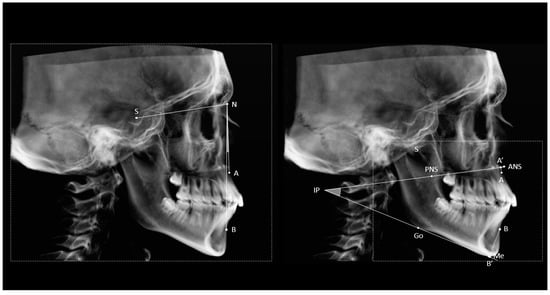

Figure 1 shows a graphic representation of the construction methods for ANB and ABwise. The projections of points A and B onto the BL line (A’) and the mandibular plane (B’) were then constructed. Finally, the distances from A’ and B’ to the IP were used to calculate the ABwise by the following formula: